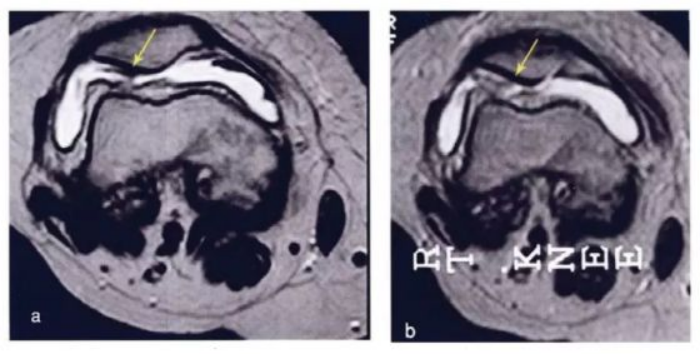

·研究结果:关节内注射骨髓间充质干细胞6个月后,,疼痛、、、功能状态和步行距离均提高。。。6名治疗组中3名患者在治疗前后的MRI比较可以看出,,,该治疗对于改善软骨厚度,,,修复组织延伸超过软骨下骨,,,以及减少软骨下骨的水肿是非常显著的。。。。

下图a示意治疗前软骨,,,,b为治疗后6个月软骨,,,,箭头所示为软骨修复位置。。。。